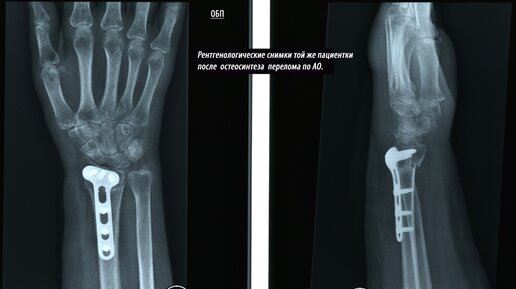

Ежегодно миллионы людей во всем мире получают перелом лучевой кости. Казалось бы, эта травма не представляет серьезной угрозы здоровью. Однако, повредив лучевую кость, пациент может столкнуться с серией неприятных осложнений. Что такое перелом лучевой кости? Это довольно типичная и распространенная травма, которая случается при падении на кисть. Такой перелом довольно болезненный и часто может приводить к осложнениям. Лучевую кость запястья можно повредить в двух случаях: при остеопорозе (болезнь,...